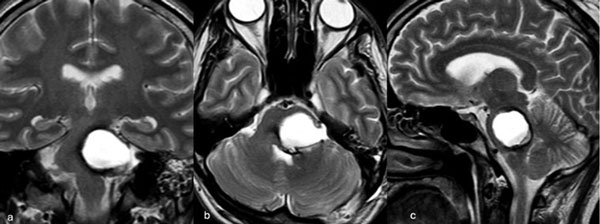

Caso 3: cavernoma pontino

Un hombre de 37 años, con antecedentes de hipertensión arterial, debutó con ataxia de la marcha, nistagmo y hemihipoestesia facial izquierda y braquiocrural derecha. La RM de encéfalo evidenció una malformación cavernomatosa centrada en la protuberancia y el pedúnculo cerebeloso medio izquierdo (Figura 6). Un mes después del sangrado, el paciente fue sometido a una exéresis de la lesión mediante un abordaje retrosigmoideo ampliado por izquierda a través del pedúnculo cerebeloso medio (Figura 7), logrando una exéresis completa (Figura 8). Después del procedimiento, el paciente evolucionó con persistencia de los síntomas de ingreso, pero sin agregar nuevos déficits.

Figura 6. RM preoperatoria de encéfalo. Se evidencia una lesión única intraaxial localizada en el puente y pedúnculo cerebeloso medio izquierdo, hiperintensa en T1 y con un anillo hipointenso en T2, característica de una malformación cavernomatosa con sangrado reciente. A) Imagen ponderada en T1 en corte sagital. B y C) Imágenes ponderadas en T2 en cortes axial y coronal, respectivamente.

Figura 7. Imágenes intraoperatorias bajo microscopía. Abordaje retrosigmoideo ampliado a izquierda, con ruta de ingreso transpedúnculo cerebeloso medio. A) Apertura de fisura horizontal que divide los lóbulos semilunar superior y semilunar inferior del cerebelo, exponiendo el pedúnculo cerebeloso medio. B) Corticotomía en pedúnculo cerebeloso medio, evidenciando la cápsula del cavernoma. C) Resección en bloque de la malformación cavernomatosa. D) Revisión del lecho, sin remanente.

Figura 8. RM postquirúrgica de encéfalo. Se evidencia una exéresis completa, sin daño del parénquima adyacente. A, B y C) Imágenes ponderadas en T2 en cortes coronal, axial y sagital, respectivamente.